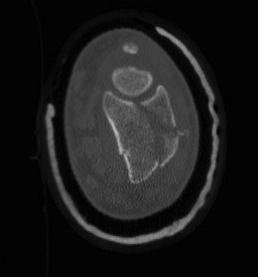

Distal Radius Fracture Articular Step Coronal CTDistal Radius Fracture Articular Step Sagittal CT

Articular incongruency > 2 mm

Distal Radius Fracture DRUJ incongruentDRUJ FractureDRUJ Fracture CT

Sigmoid notch disruption and DRUJ instability